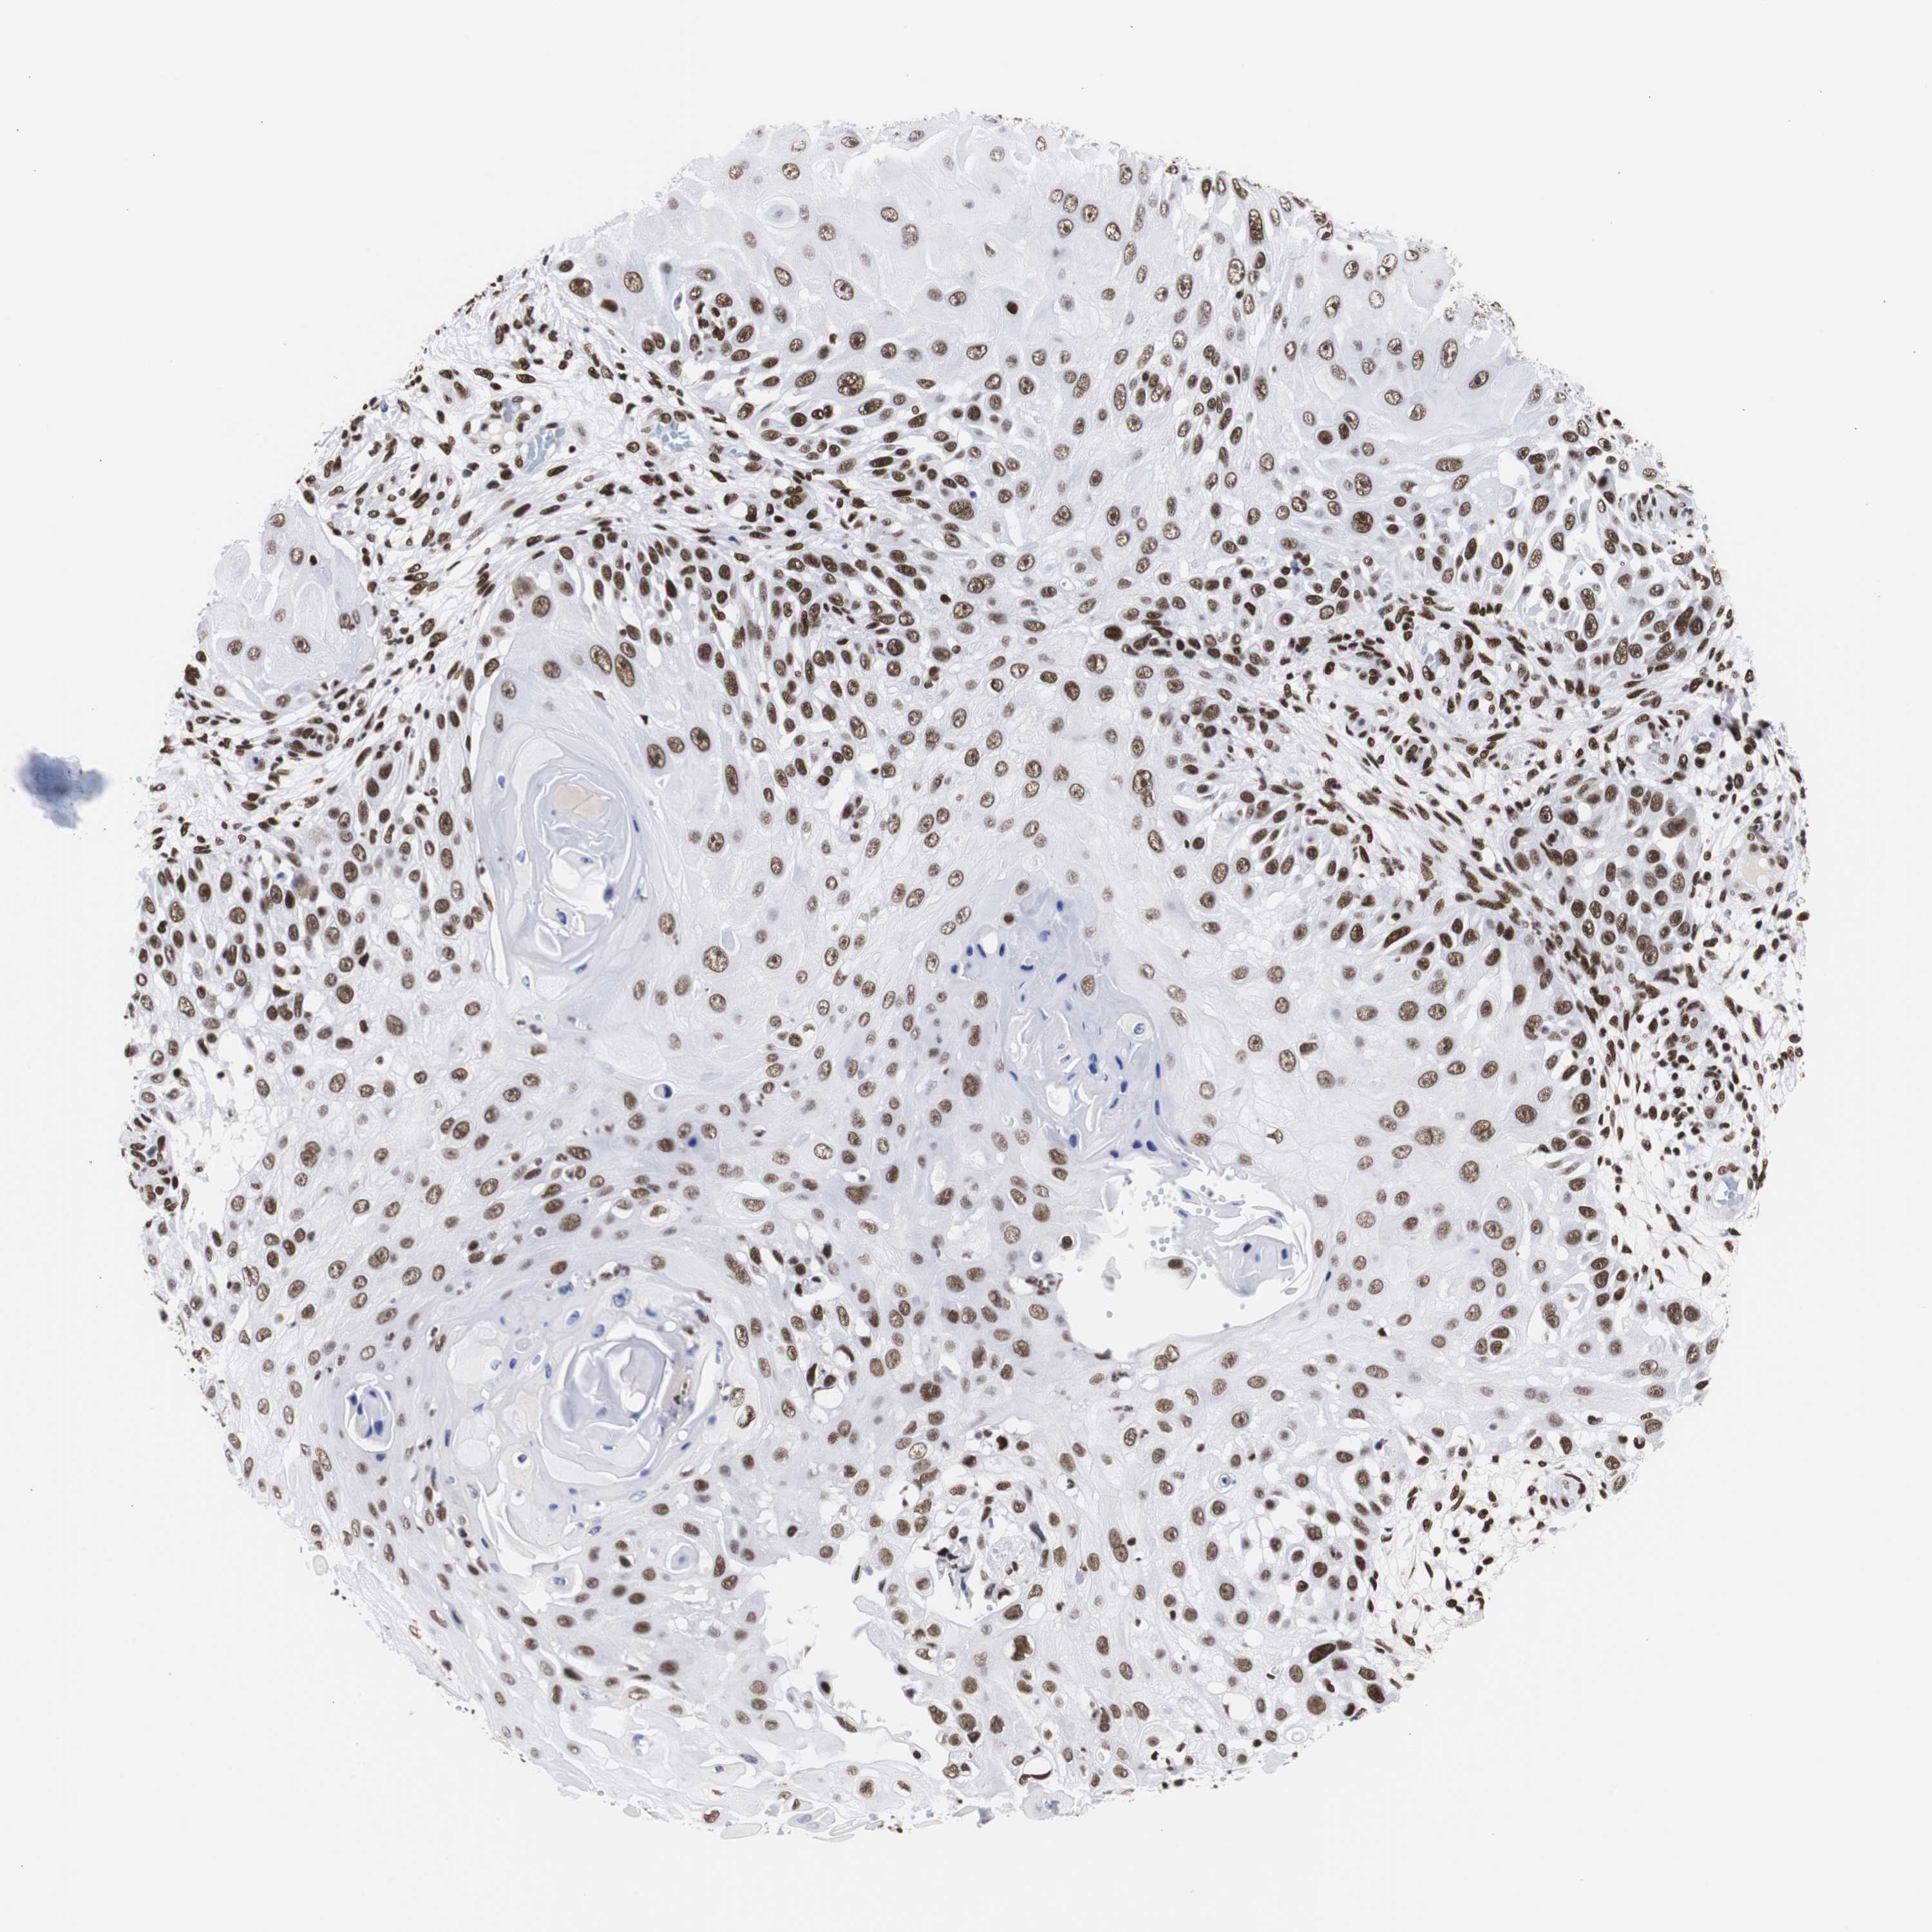

SKIN CANCER - Protein expressioni

A mouse-over function shows sample information and annotation data. Click on an image to view it in a full screen mode. Samples can be filtered based on level of antibody staining by selecting one or several of the following categories: high, medium, low and not detected. The assay and annotation is described here.

Each image is clickable and will lead to virtual microscopy that enables deeper exploration of all samples and also displays staining intensity scores, fraction scores and subcellular localization as well as patient and tissue information for each sample.

Antibody HPA001359

Staining

High

Medium

Low

Not detected

Intensity

Strong

Moderate

Weak

Negative

Quantity

>75%

75%-25%

<25%

None

Location

Nuclear

Cytoplasmic/membranous

Cytoplasmic/membranous,nuclear

Squamous cell carcinoma, NOS

Basal cell carcinoma

Squamous cell carcinoma in situ, NOS

Squamous cell carcinoma, metastatic, NOS

Adnexal tumor, benign

Papilloma, NOS